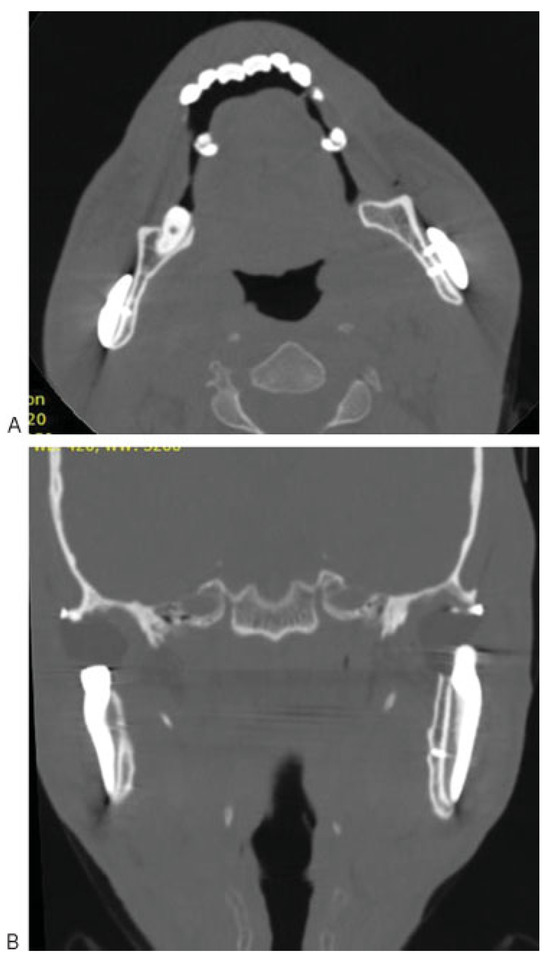

A 38-year-old man with AS was referred to the division of Oral and Maxillofacial Surgery of Piracicaba Dental School for limitation of mouth opening 16 months ago. Examination revealed that he had a 9 mm interincisal opening (Figure 1), with no lateral or protrusive mandibular movements, including severe rigidity of the cervical, thoracic, and lumbar spine. The patient reported that he underwent surgery on both shoulders in 2006 due to the joint involvement caused by the disease. In 2008, the AS affected the right iliac-femoral joint, and the patient had a femoral prosthesis inserted. The same occurred the following year with the left iliac-femoral joint. Computed tomography (CT) of both TMJs confirmed severe ankylosis (Figure 2A,B). Because of the extent of his disease, resection of the ankylotic mass and replacement of both TMJs by total alloplastic joint was indicated [9]. A stereolithographic prototype was built from the CT sections and a mock surgery was done on the prototype for fabrication of individualized prostheses (Figure 2C). The mandibular component is made of titanium, with the condylar head of cobalt–chromium–molybdenum alloy. The fossa component is designed to replace the articulating surface of the TMJ comprised by the glenoid fossa and the articular eminence. It is made of ultra-high molecular weight polyethylene. Its spherical radius allows excellent articulation to the spherical head of the mandibular component. We decided to use a customized prosthesis because it is easier to adapt at the mandibular ramus, eliminating adjustments; the occlusion is better achieved; the length of the surgery is smaller and, consequently, the morbidity and postoperative pain are reduced. Because of the rigidity of his cervical spine and limitation of mouth opening, the induction of general anesthesia was performed by fiberoptic nasoendoscopy. During the surgery, a bodily tilt of the operating table by 20 degrees on each side was required due to the rigidity of his cervical spine. Surgical access was through bilateral preauricular and submandibular incisions. Via the preauricular approach, the affected condyle was removed, the glenoid fossa was smoothed, and the articular component of the prostheses was inserted (Figure 3A,B). From the submandibular incision, the coronoid process was removed and the condylar implant inserted. The same operative sequence was done on the opposite side (Figure 4A,B). Postoperative CT confirmed correct placement of the total joint prostheses (Figure 5A,B). Wooden spatulas and a Therabite (Atos Medical, West Allis, WI) appliance were used for postoperative physiotherapy, and interincisal distance has been maintained at 20 mm at 1-year follow-up (Figure 6).

Figure 2. (A) Axial view of computed tomography (CT) showing ankylosis of temporomandibular joints (TMJs). (B) Coronal view of CT showing ankylosis of TMJs. (C) Stereolithographic prototype was built from the CT sections.